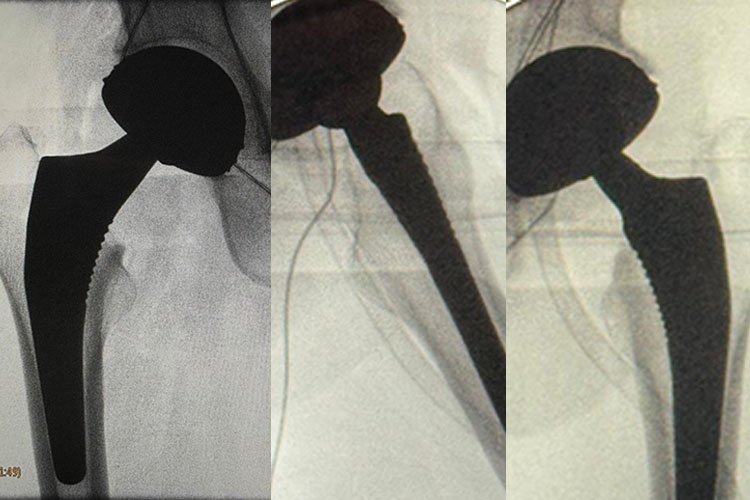

La copa metálica del sistema de doble movilidad que va incrustada en el hueso es completamente lisa en la superficie cóncava y se articula con la cabeza de polietileno.

Adentro de la cabeza de polietileno esta la cabeza metálica o cerámica.

El sistema cuenta con dos cabezas, una entra a presión en otro, se mueven entre ellas, y este conjunto se mueve además dentro de la copa metálica adherida al hueso.